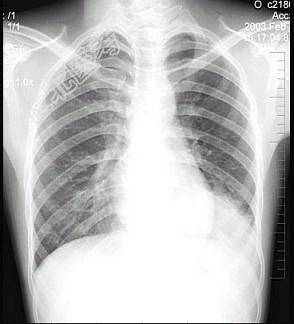

- 单项选择题男性患者,19岁, 咳嗽、发热1周,X线检查如图, 最可能的诊断是 ( )

A、左下肺不张

B、左侧胸膜肥厚

C、左下肺炎症

D、左侧胸腔积液

E、左下支气管扩张